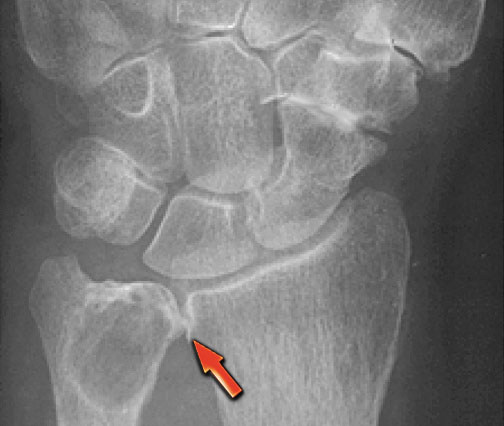

On the left images of a 30-year-old male with well-defined lytic lesion of the olecranon.

On the radiograph several ridges can be seen and a pathologic fracture (arrow).

The T2-weighted image with fat saturation demonstrates fluid-levels due to sedimentation.

Most likely diagnosis: giant cell tumor and ABC.

Biopsy revealed brown tumor.